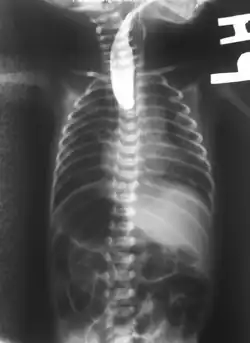

Plain X-ray of the chest and abdomen showing a feeding tube unable to move beyond an upper esophageal pouch.

On plain X-ray, a feeding tube will not be seen pass through the esophagus and remain coiled in the upper oesophageal pouch.[11]